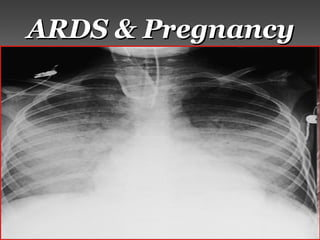

● Pregnant patients are at risk of developing ARDS fromPregnant patients are at risk of developing ARDS from

obstetric complications & from non-obstetric conditions.obstetric complications & from non-obstetric conditions.

● ObstetricObstetric complications, such ascomplications, such as amniotic fluidamniotic fluid

embolismembolism,, chorioamnionitischorioamnionitis,, trophoblastictrophoblastic

embolismembolism, &, & placental abruptionplacental abruption, can produce acute, can produce acute

lung injury.lung injury.

● Pregnancy predisposes the patient to other pulmonaryPregnancy predisposes the patient to other pulmonary

insults that can cause ARDS, such asinsults that can cause ARDS, such as gastric aspirationgastric aspiration,,

pneumoniapneumonia,, air embolismair embolism, &, & massive hemorrhage.massive hemorrhage.

● An association betweenAn association between pyelonephritispyelonephritis & the development& the development

ofof ARDSARDS has been described in pregnancy.has been described in pregnancy.

● The mechanism isThe mechanism is unclearunclear, but, but iatrogeniciatrogenic factors, such asfactors, such as

excessive fluid administrationexcessive fluid administration && tocolytic therapytocolytic therapy,,

might be responsible.might be responsible.

● TheThe reduced albuminreduced albumin level & resultantlevel & resultant reduced plasmareduced plasma

oncotic pressureoncotic pressure occurring in pregnancyoccurring in pregnancy lowerslowers thethe

critical pulmonary capillary pressurecritical pulmonary capillary pressure at whichat which

pulmonary edema develops.pulmonary edema develops.

● No major differencesNo major differences exist in theexist in the managementmanagement ofof

pregnant & non-pregnant patient with ARDS.pregnant & non-pregnant patient with ARDS.

● Fetal riskFetal risk must be considered whenmust be considered when pharmacologicalpharmacological

therapytherapy is administered.is administered.

● Adequate maternal oxygen saturationAdequate maternal oxygen saturation is essential foris essential for

fetal well-being.fetal well-being.

● Excessive alkalosisExcessive alkalosis can have adverse effects oncan have adverse effects on placentalplacental

perfusionperfusion, while, while maternal acidosismaternal acidosis appears to beappears to be

reasonablyreasonably well toleratedwell tolerated by theby the fetus.fetus.

● SurvivalSurvival appearsappears similarsimilar to ARDS in the generalto ARDS in the general

population.population.